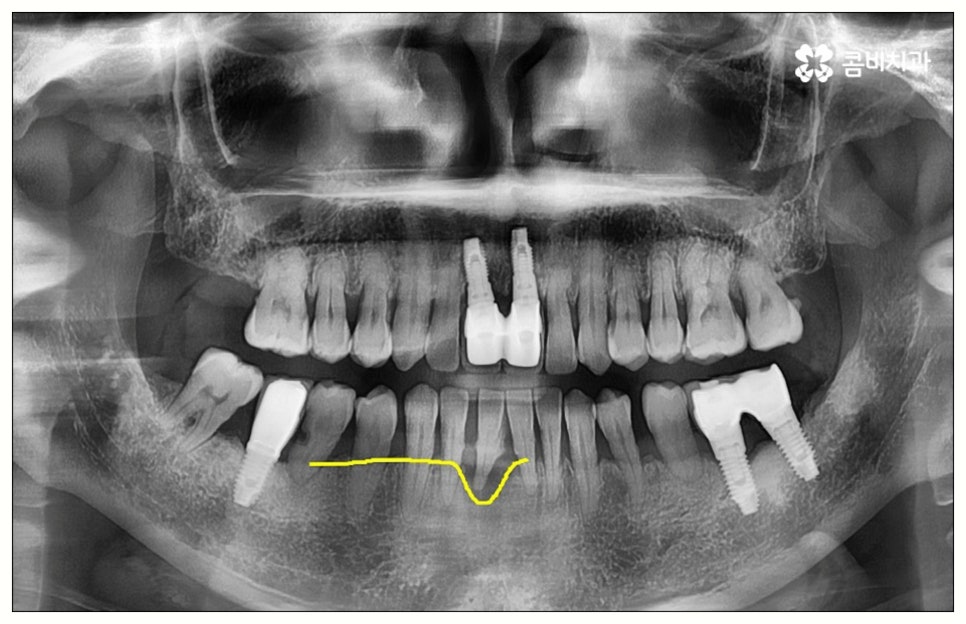

그러나 모든 환자분들이 원데이임플란트 방식을 이용할 수 있는 것은 아니기 때문에 주의하실 필요가 있어요. 말씀드렸던 것처럼 임플란트 수술은 직접 환자의 잇몸뼈에 식립을 진행하는 방식의 치료이기 때문에 잇몸뼈 상태가 양호하지 않은 분들의 경우 발치 후 바로 임플란트를 심는 것이 식립 성공률이나 지속적인 안정성 측면에서 좋지 않을 수 있어요. 특히 잇몸 질환으로 인해 염증이 심한 경우 또는 바탕이 되는 잇몸뼈의 밀도나 높이가 많이 부족한 경우에는 원데이임플란트 방식이 불가능하다고 할 수 있는데요.

이때 만약 무리하게 즉시 식립을 진행하게 되면 임플란트 치아가 제대로 기능하기 어려울 뿐 아니라 주위염 등 부작용을 일으킬 가능성이 높아 주변 잇몸 및 치아에도 좋지 않은 영향을 주게 되며 결국 임플란트가 흔들리거나 빠지면서 재수술이 필요한 상황까지 이를 수 있으므로 필요한 치료부터 선행하는 것이 좋을 거예요. 위에서 예로 든 상황이라면 잇몸 염증을 먼저 꼼꼼하게 치료한 후 또는 뼈이식술을 통해 안정성을 높인 후에 임플란트 식립을 진행하실 필요가 있어요. 이 과정에서 무엇보다 중요한 것은 수술 전 3D CT를 통해 환자의 상태를 정확하고 꼼꼼하게 확인하고, 환자의 연령, 치아를 상실하게 된 원인 및 시기, 식습관 등 관련된 모든 부분을 빠짐없이 검토하여 각자에게 꼭 맞는 계획을 세운 다음 회복 정도를 체크해 가면서 무리하지 않게 진행해 나가는 것이기 때문에 정밀 진단 장비 및 숙련된 의료진이 있는 치과에서 임플란트 치료를 받으시도록 권유드리고 있습니다.